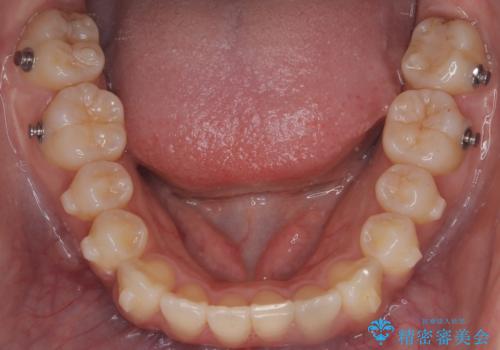

前歯の叢生・Ⅱ級咬合を改善|TADを用いた遠心移動+インビザライン矯正

- 前歯のガタガタと臼歯関係のⅡ級(上顎の歯列が前方にある状態)を改善するため、TAD(歯科矯正用アンカースクリュー)を使用したインビザライン矯正を計画しました。まずTADを上顎の適切な位置に設置し、それを固定源にして奥歯を後方(遠心)へ移動させ、十分なスペースを確保します。その後、インビザラインによるマウスピース矯正で前歯の歯列を整え、臼歯関係を正常化します。治療期間はおよそ1年半〜2年を想定しています。

前歯部の叢生(ガタガタ)と臼歯関係のズレを改善するため、抜歯をせずに奥歯を後方へ移動(遠心移動)させることを選択しました。TADという小型のアンカースクリューを顎骨に設置することで、確実かつ効率的に奥歯を後方へ移動させました。併せて透明で目立ちにくいインビザラインを用いることで、審美性を保ちながら治療を進めることが可能でした。患者様の負担が少ないマウスピース矯正と固定源のTADを組み合わせることで、抜歯することなく歯並びと噛み合わせを大幅に改善でき、大変ご満足いただけました。